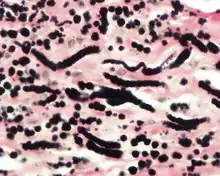

An elastic stain photomicrograph at high power highlighting the elastic fibers in black.

The elastic fibers will be highlighted by a Weigert or von Gieson elastic stains.[8]